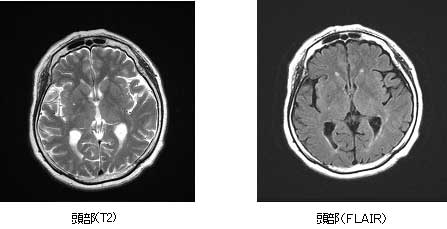

頭部領域

頭部領域では、様々な撮影法を組み合わせて診断する事で、脳梗塞、脳腫瘍、脳出血、その他の変性疾患の評価に有用です。

また、造影剤を使用する事なく血管を描出する事ができ、脳動脈瘤、血管の狭窄や塞栓の診断に力を発揮します。